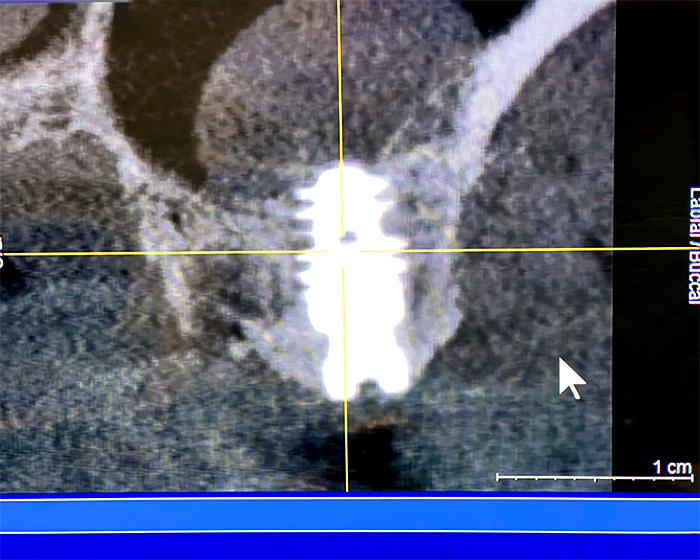

3-dimensionales Röntgen

DVT = Digitaler Volumen Tomograph

CBCT = „Cone Beam Computer-Tomography“

Auf dem Bild 1 und 2 kann man feststellen, dass die Wurzel in unmittelbarer Nähe des Unterkiefernervs (Nervus mandibularis) liegt und dass beim Operieren äusserste Vorsicht geboten ist.

Auf dem Bild 1 ist hinten am Weisheitszahn (8-er) eine Knochentasche sichtbar. Diese ist eine Folge vom Knochenabbau, welcher seinerseits eine Folge der Entzündung, welche wiederum ihrerseits durch Bakterien hervorgerufen worden ist. Diese haben sich unter die Schleimhauthäutchen eingenistet, welche oft den Weisheitszahn bedeckt.

Bild 2

Im Gegensatz zum 2-dimensionalem Röntgenbild kann man auf dem 3-dimensionalen DVT- Röntgen sehr gut unterscheiden, welche Wurzel bukkal (an der Wangenseite), lingual (an der Zungenseite) oder palatinal (auf der Gaumenseite) liegt und damit eine genaue Diagnose stellen.